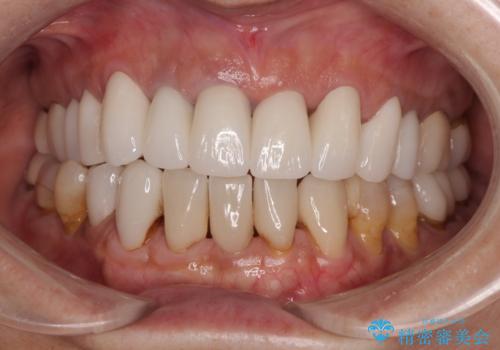

20年以上前から、むし歯になったり詰め物が欠けたりする度に部分的に処置を行ってきたそうですが、この際統一感のある前歯にしたいとのことで、上顎前歯9本をオールセラミッククラウンによる補綴治療を行うこととしました。

色調が統一されるだけでなく、歯肉ラインに見えていた茶色の境目も綺麗に改善されました。